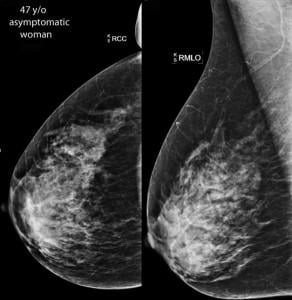

SonoCiné’s technology is engineered specifically as an adjunct to mammography in order to detect mammographically occult breast lesions in women with dense breast tissue. The AWBUS system utilizes a robotic ultrasound probe carrier and positioning gantry with angle sensors, accelerometers and gyroscopic motion control. These features record thousands of equally-spaced images of the entire breast. Combined with the company’s PACS-compatible CinéDetect software, recorded images are subsequently reviewed in a format designed to maximize the conspicuity of suspicious lesions.